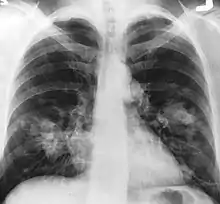

An X-ray scan indicating abnormal masses in the lungs. | |